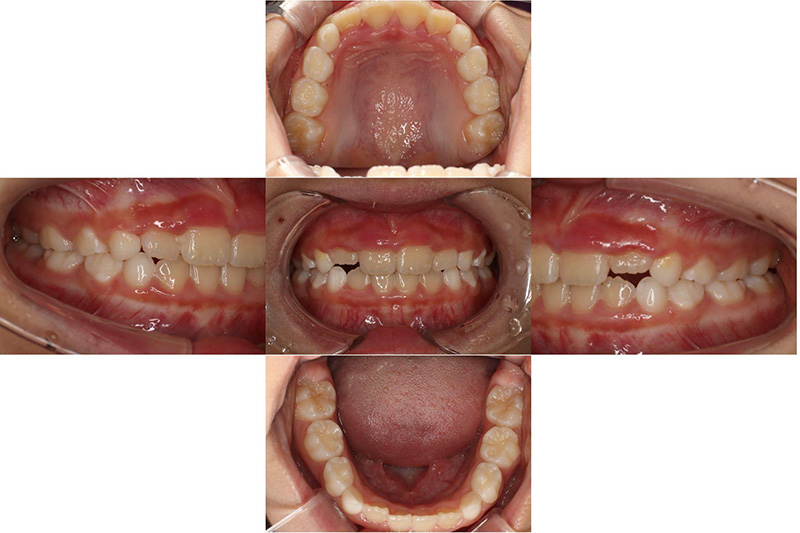

治療前

治療後

| 治療内容 | プレオルソタイプ1を日中1時間と夜間就寝時装着それに加え口腔周囲筋のトレーニング |

|---|---|

| 治療期間・回数 | 約12ヶ月、12回 |

| 費用 | 約11万円 検査費用含む |

| 副作用リスク | 後戻り 歯の痛み 歯の動揺 咬合違和感 |